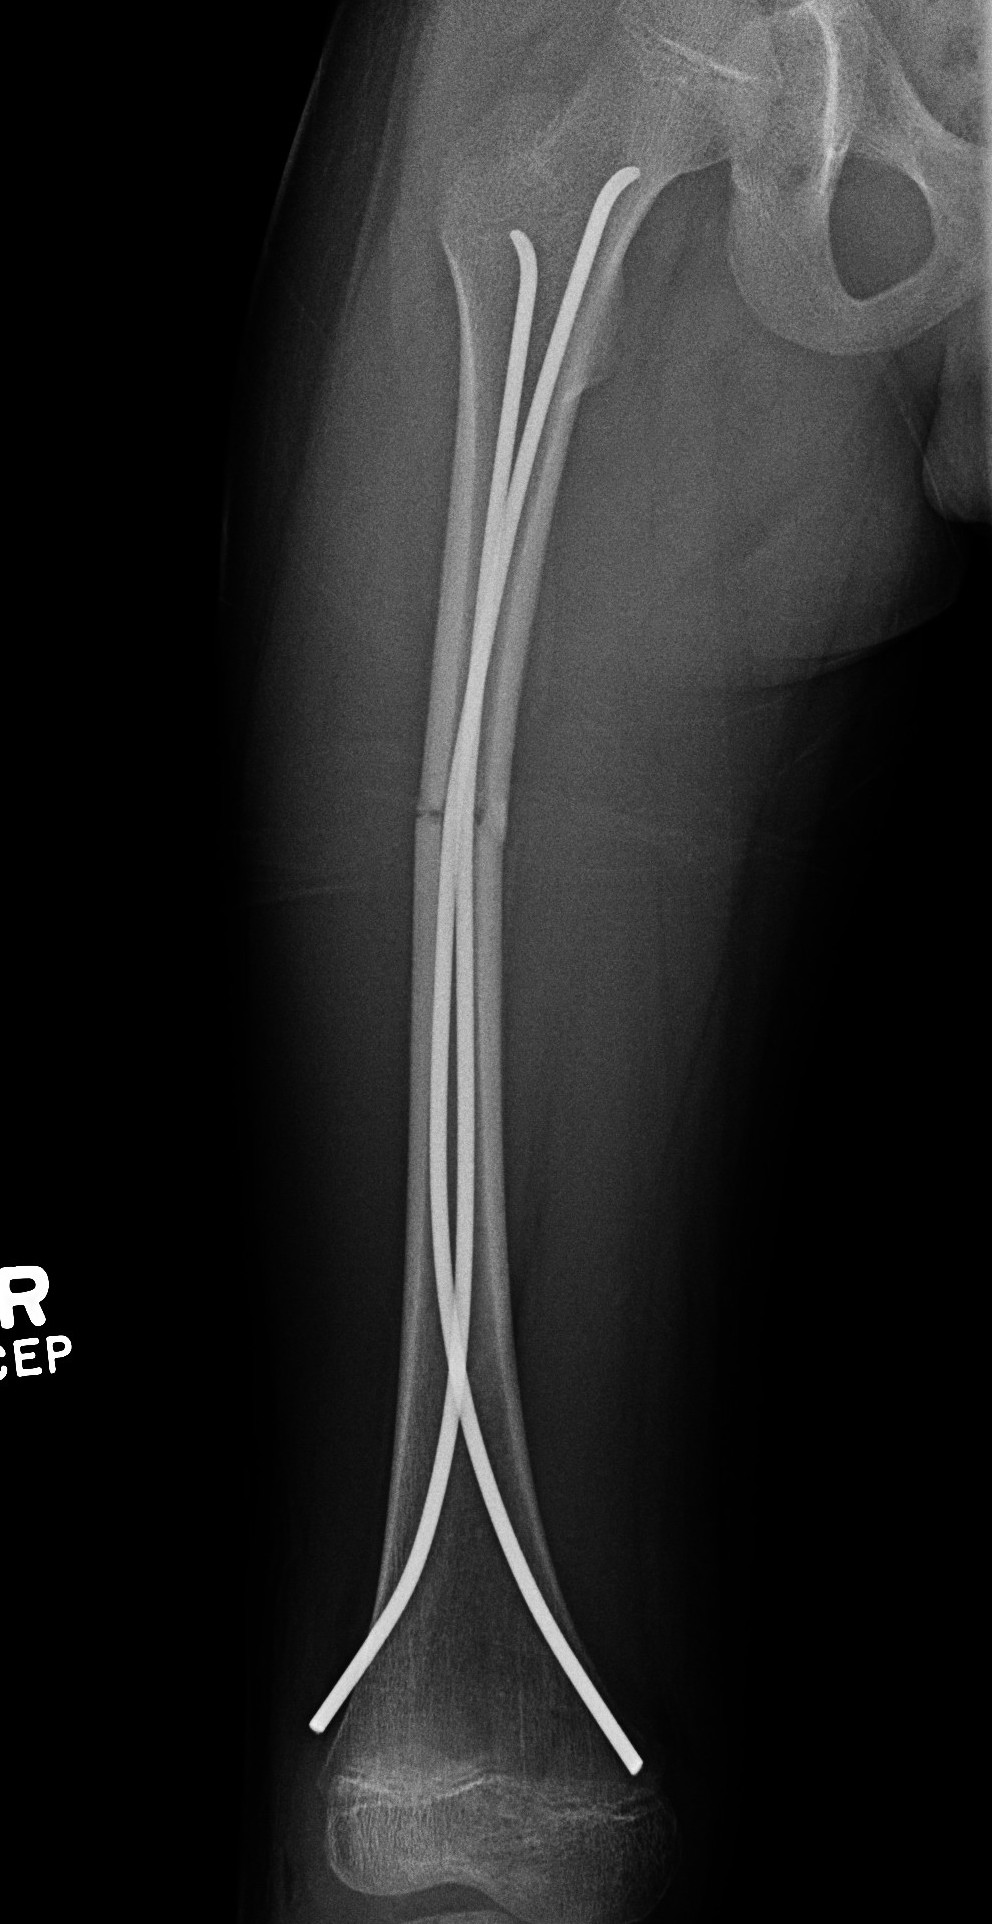

Flexible nails / Titantium Elastic Nails

Indications

Length stable fractures i.e simple transverse, short oblique

Midshaft fractures

Maximum weight up to 50 kg / 12 years old

Flexible nail technique

Wires

- available 1. 5 mm - 4.0 mm

- 30 - 40% of diameter of diaphyseal medullary canal

- i.e. if canal 10 mm wide, use 2 x 4 mm

- recommend using 2 wires same diameter to avoid rotational instability

Entry points

- medial and lateral insertion

- 1 - 2 cm proximal to distal femoral physis

- oblique entry with awl in direction of nail insertion

- can open with drill bit

- beware proximity of the femoral artery medially

- entry points should be symmetrical

Wire passage

- bend wire for 3 point fixation with bend at fracture site

- also bend the tip of the wire

- can use F Tool to reduce fracture / sheet in groin

- may need small incision and open reduction

- medial entry wire will pass into femoral neck

- lateral wire will pass into greater trochanter / medial wire into femoral neck

- use designated TEN wire cutter to cut wires

- cut off, tap in slightly further, leave 1.5 cm out so can retrieve

- wires that are too prominent can cause bursa / limit flexion / pain / protrude through skin

Acceptable alignment

- 10o varus / valgus

- 15o flexion / extension

- 15 mm shortening